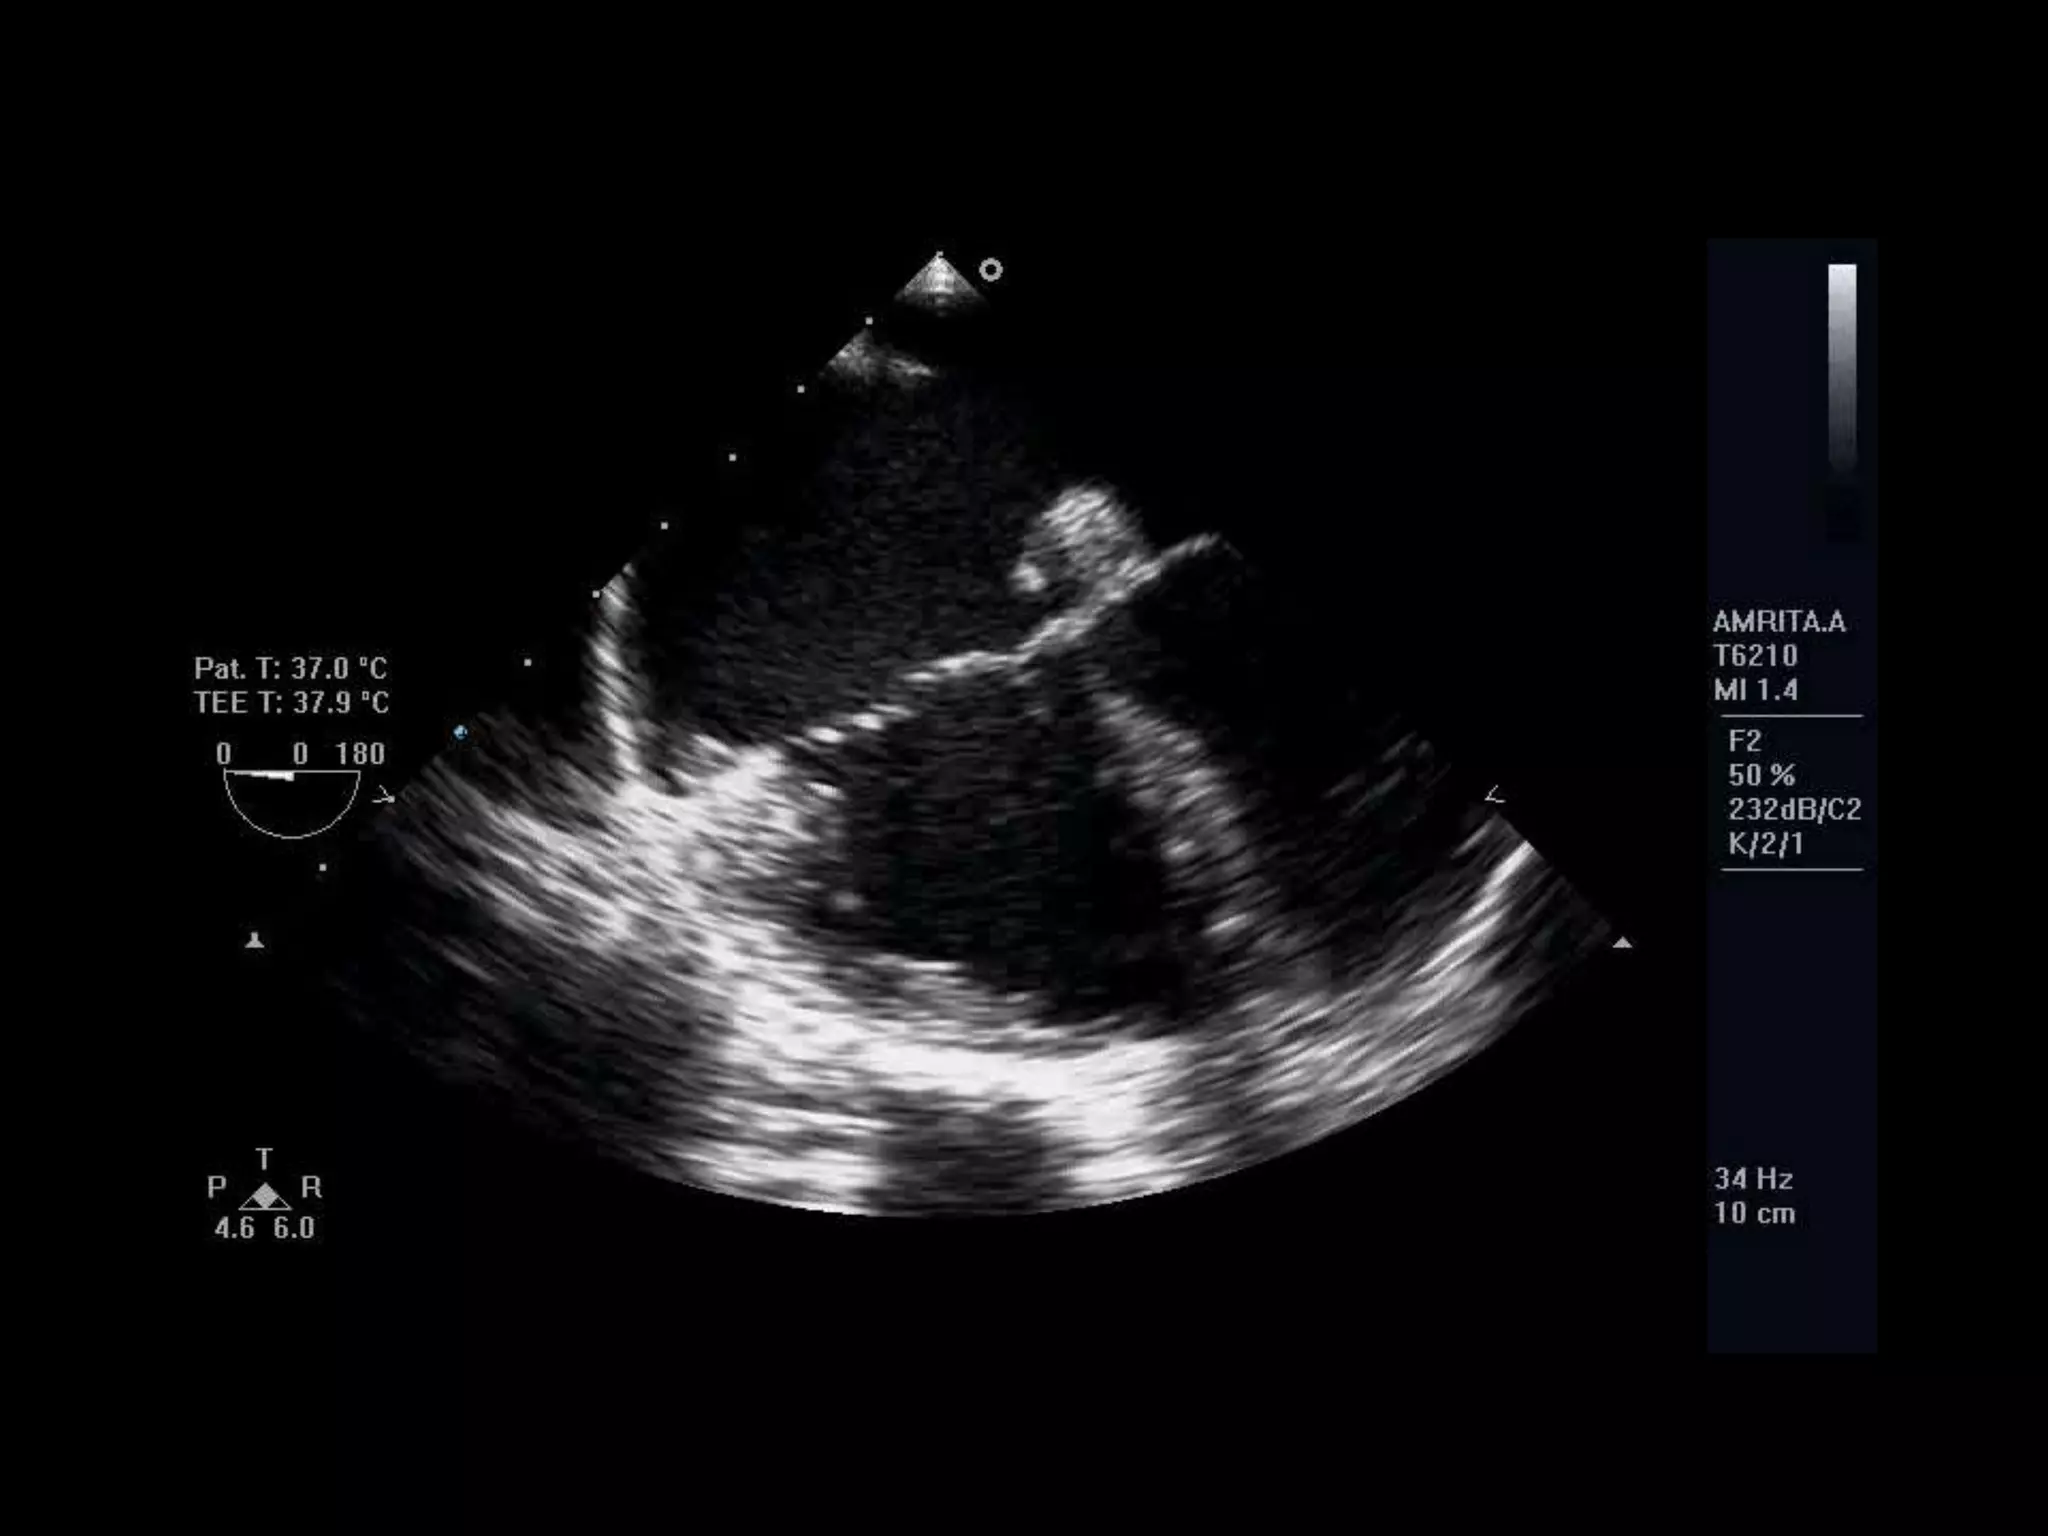

TEE 4-chamber view depicting an adequate

posterior rim for percutaneous closure of

20 mm.

Transesophageal 4-chamber view:

The AV rim measures 9.5 mm, which

is adequate for PCT

TEE 4-chamber viewdepicting an adequate posterior rim for percutaneous closure of 20 mm. Transesophageal 4-chamber view: The AV rim measures 9.5 mm, which is adequate for PCT